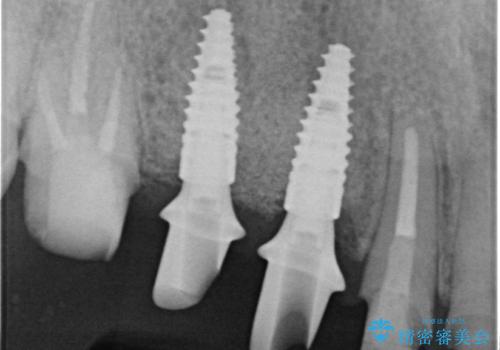

歯周病や虫歯・強度の問題がありながらも無理やり残していた長期的な予後の見込めない歯を抜去し、インプラントを用いてしっかりと噛めるような口腔内環境の確立を目指します。

- 176万円(インプラント×4・チタンカスタムアバットメント×4・ジルコニアクラウン×4・仮歯×4)費用は治療当時の料金となります